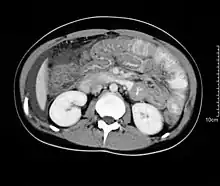

Hypereosinophilia, the hallmark of allergic response, may be absent in up to 20% of patients, but hypoalbuminaemia and other abnormalities suggestive of malabsorption may be present. CT scans may show nodular and irregular thickening of the folds in the distal stomach and proximal small bowel, but these findings can also be present in other conditions like Crohn's disease and lymphoma.